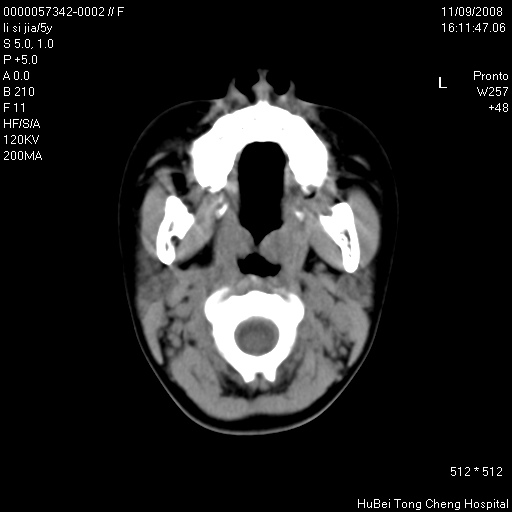

患儿 女,5岁。鼻塞、流涕2年余。

临床诊断:慢性副鼻窦炎?

副鼻窦ct轴位平扫(层厚、层距均为5mm),图像如下:

双侧上颌窦\\筛窦及蝶窦内均可见多量软组织密度影,结合病史支持考虑慢性全鼻窦炎

双侧上颌窦、筛窦及蝶窦内均可见粘膜增厚,结合病史支持考虑慢性全付鼻窦炎,腺样体肥大。

1、上颌窦、筛窦、蝶窦炎。2、腺样体肥大